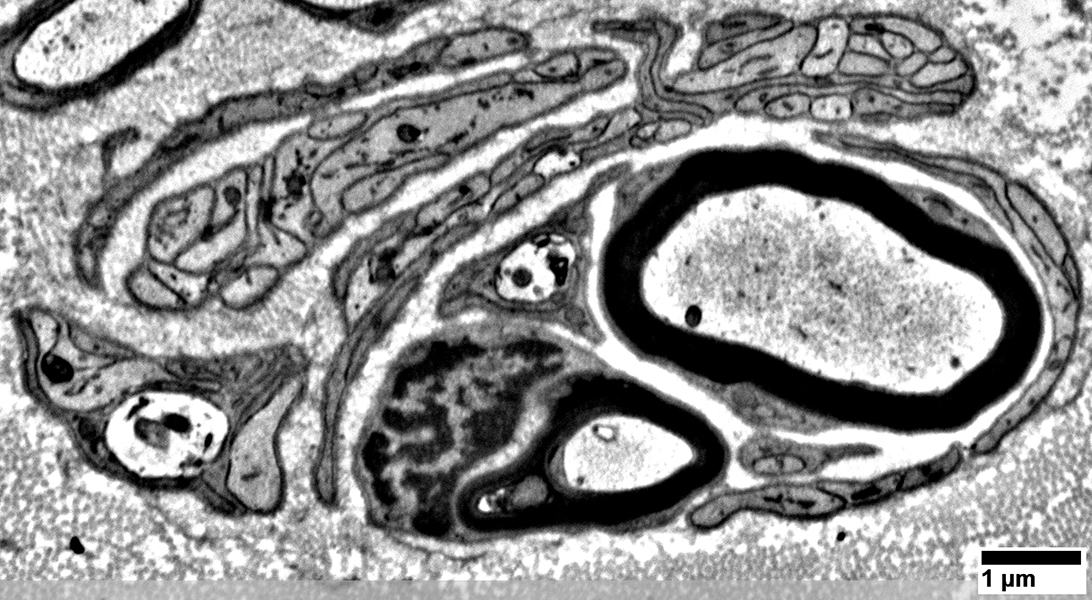

Pseudo-Onion bulbs: Ultrastructure

Pseudo-Onion bulbs

Multiple, complex, interdigitated Schwann cell processes surround regenerated, thinly myelinated, axons

From: Chunyu Cai

Multiple Schwann cell processes surround regenerated, thinly myelinated, axons